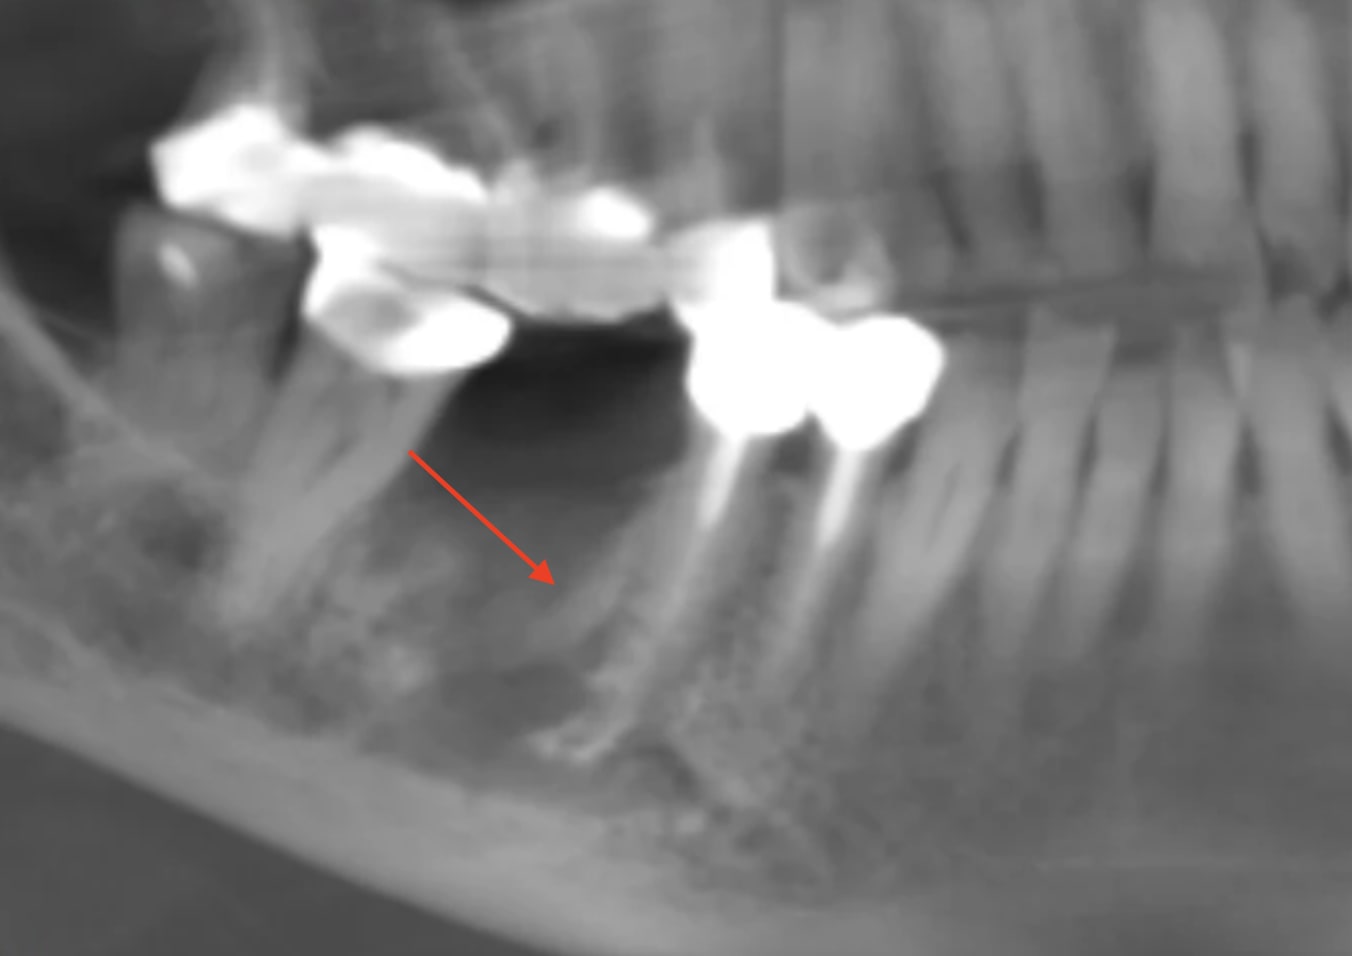

559940449_10163144646462247_7720006236309727129_n.jpg